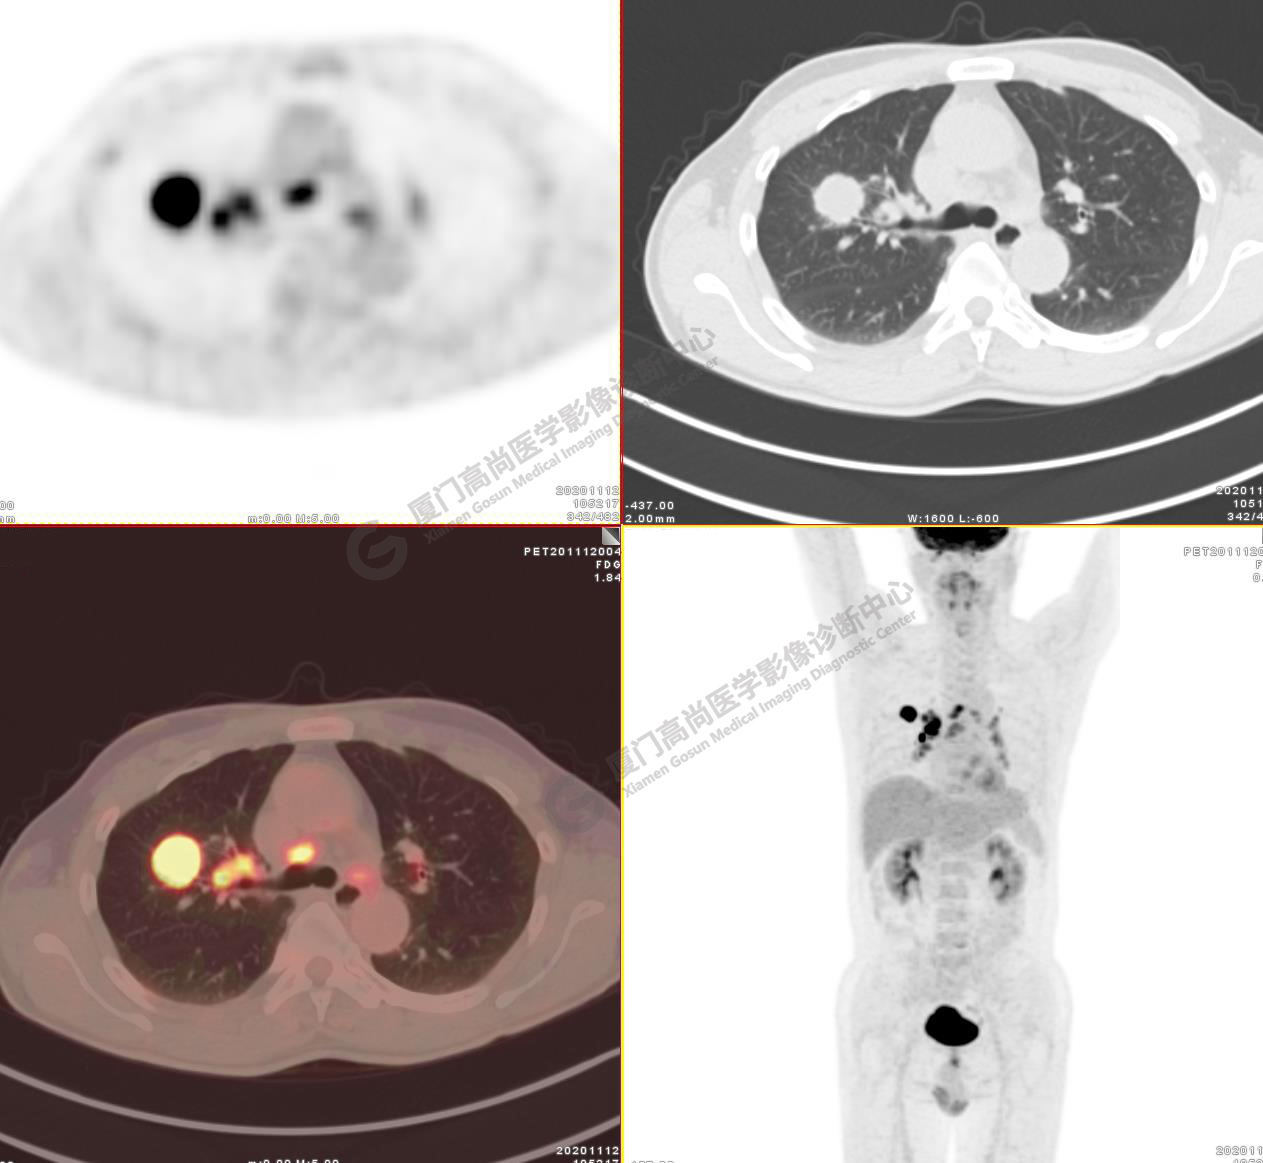

病例2:某男士,53歲,2020年4月單位體檢,CT,發(fā)現(xiàn)右肺上葉結(jié)節(jié),性質(zhì)待定

右肺上葉前段見一類圓形實(shí)性結(jié)節(jié),大小約2.8x2.6cm,邊緣見分葉、毛刺,前段支氣管阻塞。FDG攝取增高,SUVmax16.5,右肺門及縱隔見多發(fā)腫大淋巴結(jié), FDG攝取增高,SUVmax13.1,遠(yuǎn)處未見FDG高攝取病灶 。

影像診斷:右肺上葉周圍型肺癌并右肺門及縱隔淋巴結(jié)轉(zhuǎn)移。

( TNM分期,T1cN2M0 ⅢA期)

病理診斷 :低分化腺癌